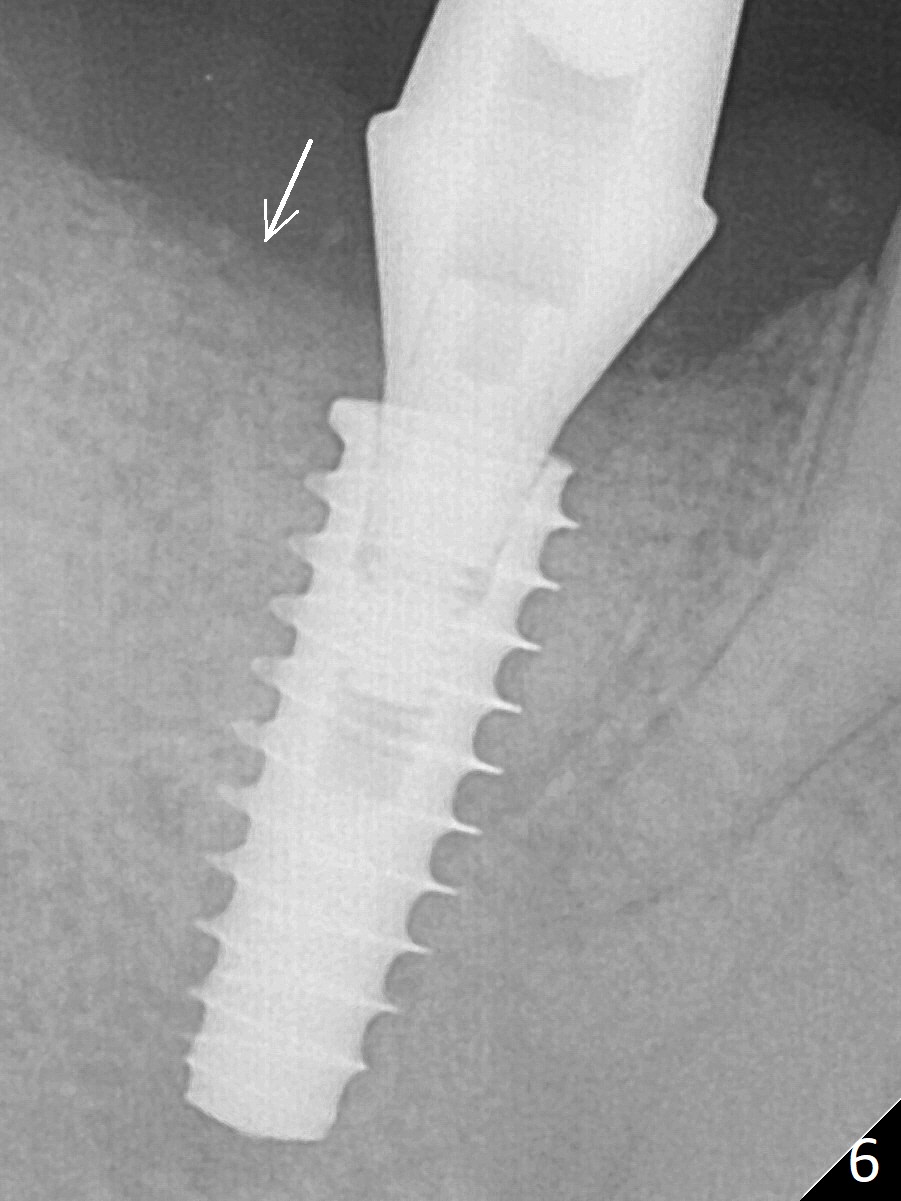

Bone graft seems to sink down and becomes denser 3 months postop (Fig.6 arrow).